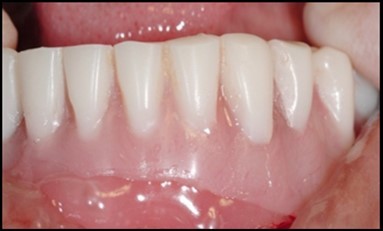

Figure 2.Prpre-operative view of anterior mandibular knife edge ridge.

Prpre-operative view of anterior mandibular knife edge ridge.